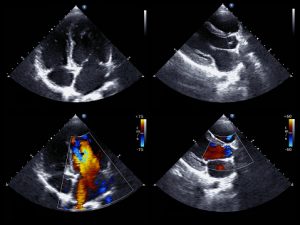

Diagnosing cardiac sarcoidosis often involves positron emission tomography (PET) scans and computed tomography (CT) scans, but results are often difficult to interpret.

For the scans, patients must be first injected with a short-lived radioactive tracer called fludeoxyglucose (FDG), which is similar to glucose. FDG concentrates in cells with high metabolic rates (e.g., cancer cells, neurons) and cells affected by inflammation.

In order to reduce the amount of sugar and FDG absorbed by healthy heart cells, patients are often asked to consume a high-fat and low-sugar diet 24 hours before the test. Healthy heart cells use fat for fuel so that the cells affected by disease use the sugar and thus stand out more clearly on the resulting images.

Dr. Lu added, “When we used this method, we noticed that the results were not satisfactory. The unpredictable uptake of FDG by healthy heart cells makes the scans hard to read.” Almost half of the scans preceded by the 24 hours of the special diet were not useful for diagnosis.

Following these findings, the researchers wanted to determine whether 72 hours on the diet would further improve imaging results. Compared to the 24-hour diet group with 42 percent having undetermined results, the 72-hour diet group only had four percent of patients with unclear results. This suggests that being on the high-fat low-sugar diet for a longer period helps improve the accuracy of diagnosis.